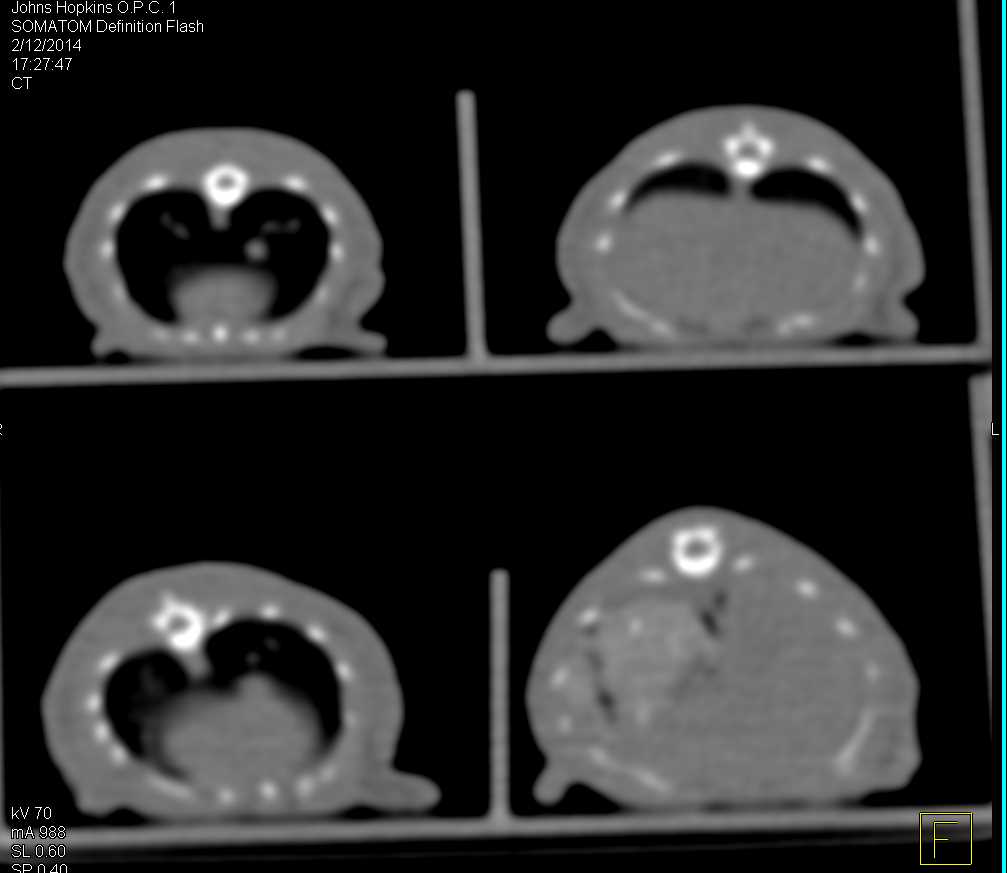

Osteomyelitis Left Shoulder Joint in a Mud Turtle